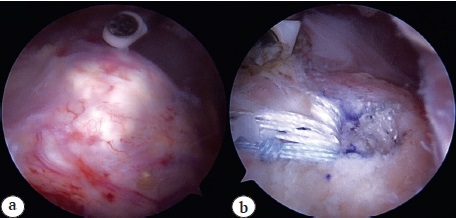

Fig. 5. Case 2. Calcific tendinitis of the supraspinatus tendon: a — calcification; a — calcification; b — refixed supraspinatus tendon after removal of the calcium deposit